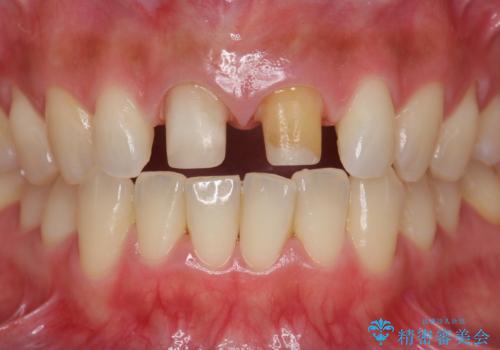

- 3週間後に迫った結婚式までになんとか前歯をきれいにしたいという希望で来院されました。

一回の治療時間を長く取り、限られた時間で最大限の結果を出せるよう集中治療を計画します。

ただ見えるクラウンを白くきれいにするのではなく、長期的な歯の予後を考えると根管治療・ファイバーコア築盛・精密な歯牙形成等クリアすべき条件は多々あると言えます。